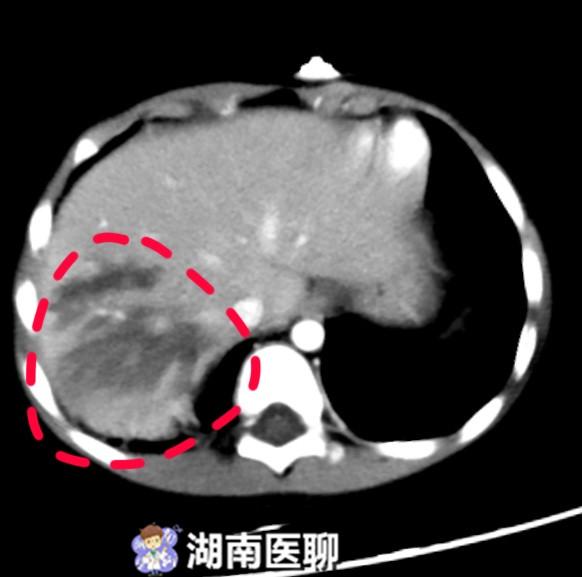

肝挫伤及包膜下血肿的ct表现